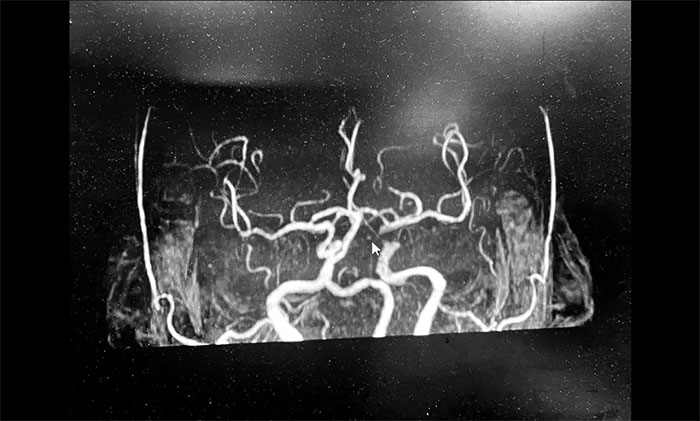

神经内科3A病区周君主任详细了解病史,查体,并为韩老伯完善相关的检查。头颅MRI示:脑干及双侧大脑半球多发陈旧梗死灶,左侧胼胝体、半卵圆中心、侧脑室旁及额叶多发梗死灶,偏亚急性期。脑动脉硬化,颅底动脉多发不同程度狭窄(左侧颈内虹吸段为著)。

▲ 头颅MRI示:左侧多发梗死灶,左侧颈内动脉狭窄

周君主任表示,从影像学上,患者左侧脑室旁散在多个新鲜梗死灶,呈比较典型的“分水岭样梗塞”表现。分水岭样梗塞(Watershed infarction,WI),是指发生在脑部两条主要动脉分布区的交界处的脑梗死,多发生于脑部较大动脉供血交界区。

韩老伯的新发病灶处在左侧颈动脉供血支配范围内,符合因左侧颈内动脉狭窄而造成脑组织缺血表现,需要针对这一引起脑梗的病因,及时采取干预治疗措施。